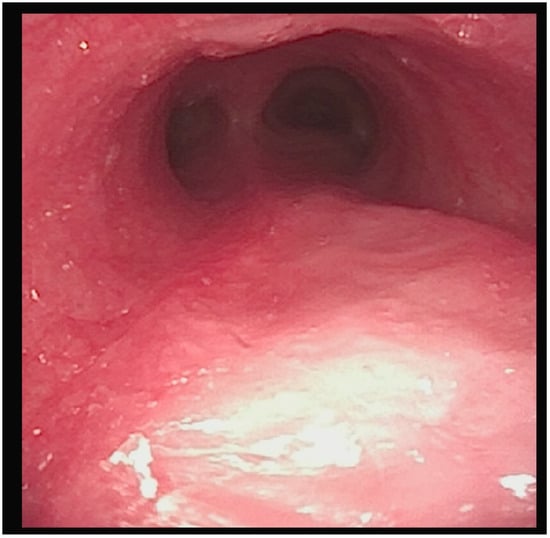

After this comprehensive approach, the patient’s tracheal obstruction episodes resolved, and the granulomatous tissue showed significant regression (Figure 3).

Figure 3. Image taken after 3 months of specific cannula management.